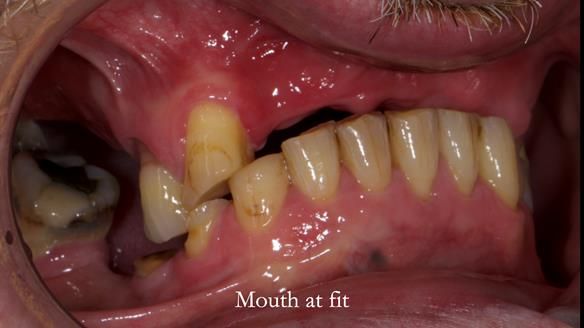

Keith’s case was one of the most challenging and rewarding cases I’ve treated this year. This 64 year old man presented with ill-fitting acrylic partial dentures that lacked stability, retention, and aesthetics. They constantly broke. He had lost the upper front teeth in a road traffic accident in his early 20s. The unopposed teeth had erupted, taking up space. After careful planning, we made a durable, metal-based upper partial denture/splint to address his dental concerns. He loved the outcome.

4. Keith’s outcome: The final denture not only improved Keith’s bite, chewing function, and facial aesthetics but also protected his remaining teeth from further damage.

I also used the Dahl concept to re-establish the occlusion upon fitting the RPD, which helped to intrude the lower left canine without needing to grind it too much.